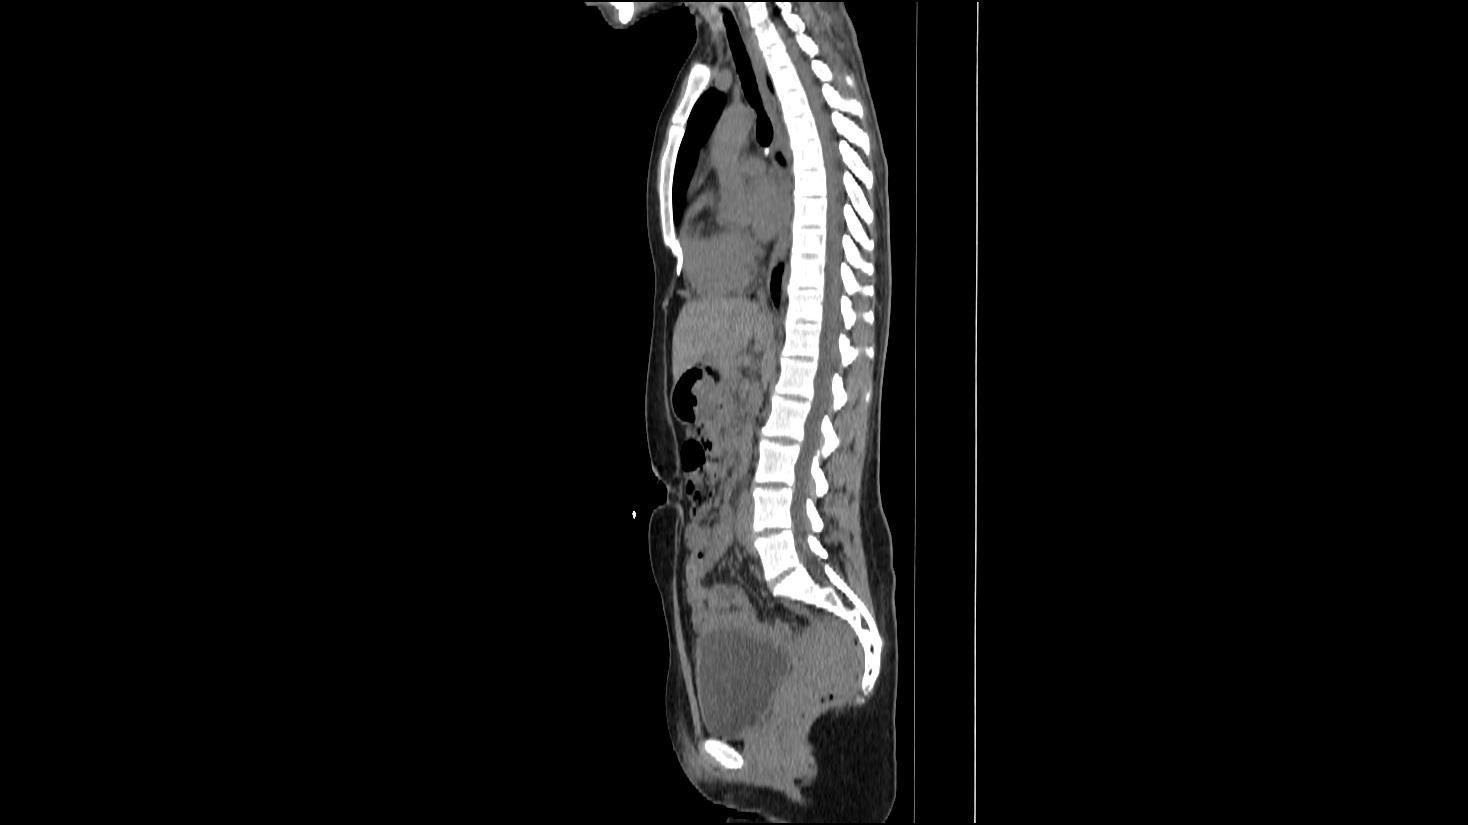

A Full Body Scan That Discovers Problems Before They Advance

A full body scan delivers a fast, detailed look at your internal organs, giving you insight into concerns that often grow unnoticed. This type of screening can reveal tumors, cysts, stones, inflammation, and other abnormalities that rarely cause symptoms in the early stages. Because many conditions progress quietly, full-body imaging is one of the most effective ways to stay informed and proactive.

With high-resolution CT imaging, your scan can uncover issues that routine exams, blood work, and physicals may overlook. You gain clarity about your health, the chance to address concerns early, and reassurance when everything appears normal.